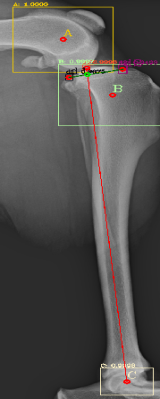

Most of the source dataset of over a thousand unique knee radiographs were distorted, had poor patient positioning, or were otherwise unfit for annotating. 250 of the original images were of sufficient quality to contribute to this effort. These images were set to have 6 different classes for training purposes, as mentioned and shown in Fig. 4. These were then trained using YOLOv3 [10] and the results of the predicted annotations are shown in Table I. From these predictions the centroids were extracted, which is then used to plot the FTL and MTPL. Then using the method mentioned in Section II, TPA is calculated. Examples of images, the region of interests detection and their respective TPA determination is shown in Fig. 6 and Table I:

| Image | YOLOv3 | YOLOv4-1 | YOLOv4-2 | YOLOv4-3 |

|---|---|---|---|---|

| 6(a) | 20.537° | 22.67° | 24.8° | 22.9° |

| 6(b) | 17.354° | 17.62° | 18.7° | 16.22° |

| 6(c) | 19.473° | 19.53° | 20.03° | 18.24° |

| 6(d) | 23.369° | 27.37° | 29.03° | 25.8° |

| 6(e) | 18.435° | 15.5° | 17.65° | 16.8° |

| 6(f) | 19.699° | 18.24° | 20.22° | 18.59° |

For comparison purposes the radiographs have been tested with YOLOv3, original YOLOv4 [12] and custom modifications of the YOLOv4 by changing the activation functions and the results are shown in Table II. The original version of YOLOv4 (addressed as YOLOv4-1 in Table II) combined the Mish, Linear and Leaky activation functions, the versions YOLOv4-2 and YOLOv4-3 used for the purpose of testing in this paper have combinations of Mish, Linear, Swish and Mish, Linear and Relu activation functions respectively. Similarly, comparison of the results that did not fall under the presumed normal range shown in Fig. 9, for the algorithm, are shown with variations in activation function in Table III. It can be seen here that these images, are giving TPA predictions similar to the original YOLOv3, i.e. outside of presumed range.